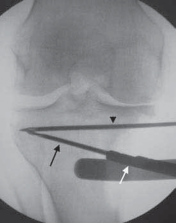

4. Using fluoroscopy, the alignment rod is placed at the center of the femoral head (

TECH FIG 3A

) and then at the center of the ankle joint (

TECH FIG 3B

).

A B F

D E TECH FIG 3•A.

Fluoroscopic image of alignment rod through femoral head.

B.

Fluoroscopic image of the alignment rod in the center of the ankle.

C.

The subsequent location of the alignment rod in the knee. This initial mechanical axis must be corrected. It should match with the preoperative planning.

D.

Initial guide pin from medial to lateral and parallel to the joint line. The pin is placed approximately 1 cm distal to the joint line.

E.

Osteotomy guide pin assembly over the initial guide pin. The angle of the guide pin assembly is changed so that the guide pins are just superior to the tibial tubercle. Two pins are drilled from medial to lateral along the osteotomy line to intersect the initial guide pin 1 cm from the lateral cortex.

F.

Fluoroscopic image verifying the two guide pins placed from medial to lateral using the osteotomy guide pin assembly. Note how in this view, which is parallel to the joint surface, the two pins are superimposed on one another, thus verifying that they, too, are parallel to the joint surface.

White arrow,

guide pin assembly;

black arrow,

osteotomy guide pins;

black arrowhead,

initial guide pin.

1. The subsequent location of the alignment rod in the coronal view of the knee is the intraoperative location of the mechanical axis (

TECH FIG 3C

2. These radiographs are saved for later comparison.

1. A guide pin is placed from medial to lateral across the proximal tibia, 1 cm distal to the joint, and parallel to the joint surface.

1. The tip of the guide pin should be just proximal to the level of the fibula. The location of this guide pin should be verified with fluoroscopy (

TECH FIG 3D